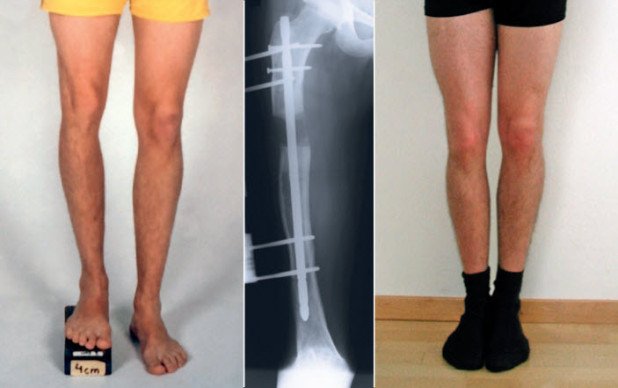

Fünf bis zehn Tage nach der Operation beginnt man mit der eigentlichen Verlängerung des Knochens. Das bedeutet, dass die Stelle, wo der Knochen durchtrennt wurde, einen Millimeter pro Tag auseinander gezogen wird. In diesem Prozess wächst zwischen den beiden Knochenenden ein so genannter Distraktionscallus, der aus einer noch nicht verkalkten und daher weichen Knochengrundsubstanz besteht. Der Callus lässt sich nun auf die gewünschte Länge dehnen. Wenn nötig, kann dabei gleichzeitig auch eine Achsenkorrektur des Knochens vorgenommen werden. Da der Knochen strikt um einen Millimeter pro Tag verlängert wird, kann der neu gebildete Knochen optimal nachreifen. Eine Verlängerung von 5 Zentimetern benötigt somit eine Verlängerungszeit (Distraktionsphase) von etwa 50 Tagen.

Nach der Distraktion muss der neue Knochen (Distraktionscallus) wieder die Struktur des ursprünglichen Knochens annehmen. Im Normalfall sieht man in den Röntgenbildern eine zunehmende Kalkdichte der Verlängerungsstrecke. Ist diese annähernd so dicht verkalkt wie der umgebende normale Knochen (siehe Deckblatt), kann der Apparat entfernt werden.

Die Knochenverlängerung ist kein schnelles Therapieverfahren. Untersuchungen haben gezeigt, dass man pro Zentimeter Verlängerungsstrecke mit ungefähr 30 bis 40 Tagen im Verlängerungsapparat rechnen muss. Dies bedeutet: Um den Knochen um 5 Zentimeter zu verlängern, muss man den Verlängerungsapparat etwa 150 bis 200 Tage lang tragen, bis der neue Knochen genügend nachgereift ist. Eine reine Achsenkorrektur hingegen, benötigt eine Tragdauer von ungefähr drei Monaten.